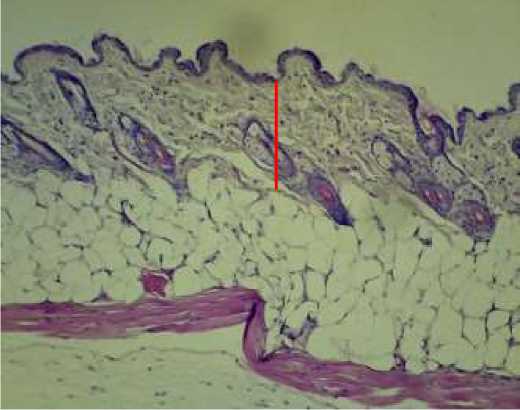

Demikian juga hasil pengamatan penampang melintang struktur histologi lapisan dermis mencit menunjukkan bahwa setelah perlakuan ovariektomi

mempunyai ketebalan dermis yang lebih tipis dan setelah pemberian ekstrak kedelai hitam

menunjukkan ketebalan dermis yang lebih tebal, seperti pada Gambar 1.

(a)

(b)

(c)

(d)

Gambar 1. Mikrograf penampang melintang dermis mencit (Mus musculus.L) unilateral ovariektomi dengan pewarnaan Hematoxylin Eosin (garis merah) (a) kontrol negatif; (b) kontrol positif; (c) dosis 1 (0,31 g/mL/hari); dan (d) dosis 2 (0,63 g/mL/hari)